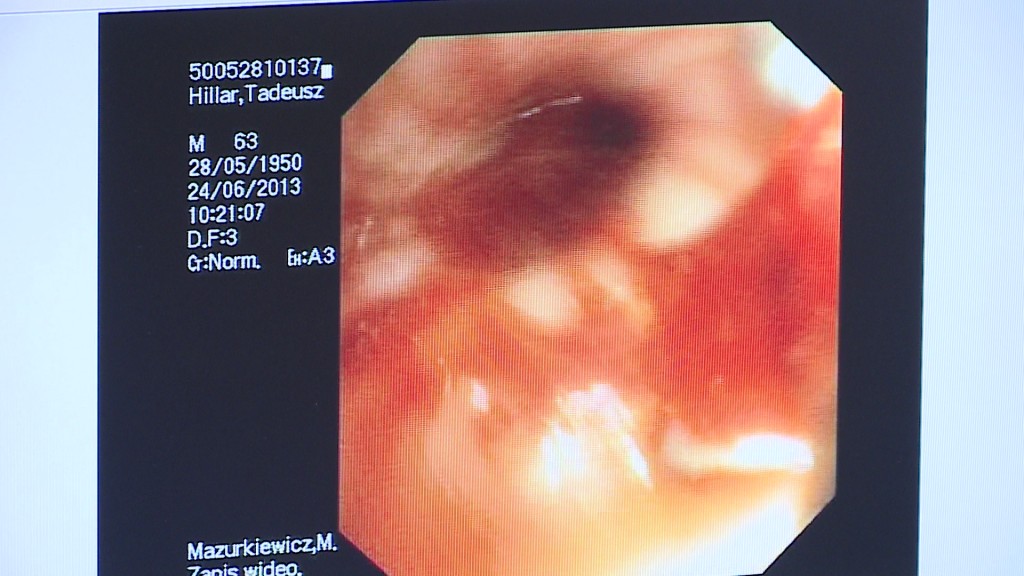

• Najważniejsze jest to co uzyskamy jeżeli chodzi o diagnostykę chorób układu oddechowego. Mamy dwie części. Pierwszą z nich jest bronchoskopia, a więc zajrzenie do drzewa oskrzelowego, obejrzenie jego wnętrza, co ma zasadnicze znaczenie w diagnostyce chorób nowotworowych. Możemy ten nowotwór nie tylko zobaczyć we wczesnej fazie, kiedy te objawy nie są mocno wyraźne. We wczesnej fazie, czyli w fazie, kiedy możemy efektywnie leczyć, możemy pobrać wycinki i rozpocząć drogę, która doprowadzi do wyleczenia pacjenta. Druga część tych pracowni to spirometria - badania czynnościowe układu oddechowego. Pomocne są one w diagnostyce chorób oskrzeli - wyjaśnia Krzysztof Bigus, Kierownik Pracowni Diagnostycznych Oddziału Chorób Płuc w Wejherowie.